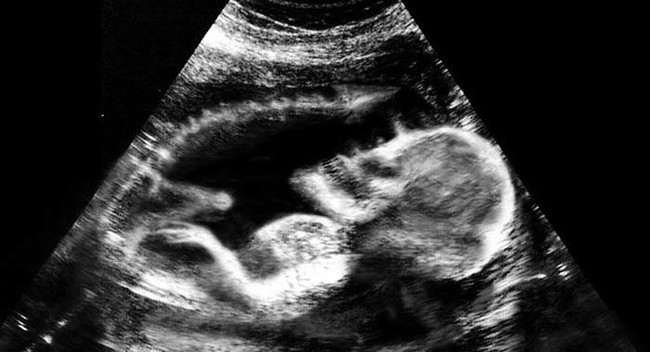

เดี๋ยวนี้ยามตั้งครรภ์คุณแม่เกือบทุกคนก็นิยมอุ้มท้องป่อง ๆ ไปให้คุณหมอทำอัลตราซาวด์ จะได้เช็กดูว่าเจ้าตัวน้อยข้างในอยู่สบายแข็งแรงดีหรือเปล่า แถมยังได้จะเห็นไปหน้าเค้าโครงใบหน้าลาง ๆ ของเจ้าหนูด้วย ดูแค่เงาก็เดาไปกันใหญ่แล้วว่าเหมือนใครมากกว่ากัน จนอดใจไม่ไหวอยากรีบคลอดออกมาให้เห็นหน้าลูกน้อยตัวจริงเร็ว ๆ แต่ถ้ามาเจอ 13 รูปอัลตราซาวด์สุดสยอง ที่เรานำมาฝากจากเว็บไซต์ boredomtherapy เหล่านี้เข้าไปหน่อยล่ะก็... บางทีคุณอาจไม่แน่ใจแล้วล่ะว่า นี่ใช่ลูกฉันจริงหรือเปล่า !!

ถึงจะรักเด็กแค่ไหน แต่ถ้าคุณขวัญอ่อนเราขอเตือนกว่าอย่าเลื่อนลงไปดูดีกว่านะ...